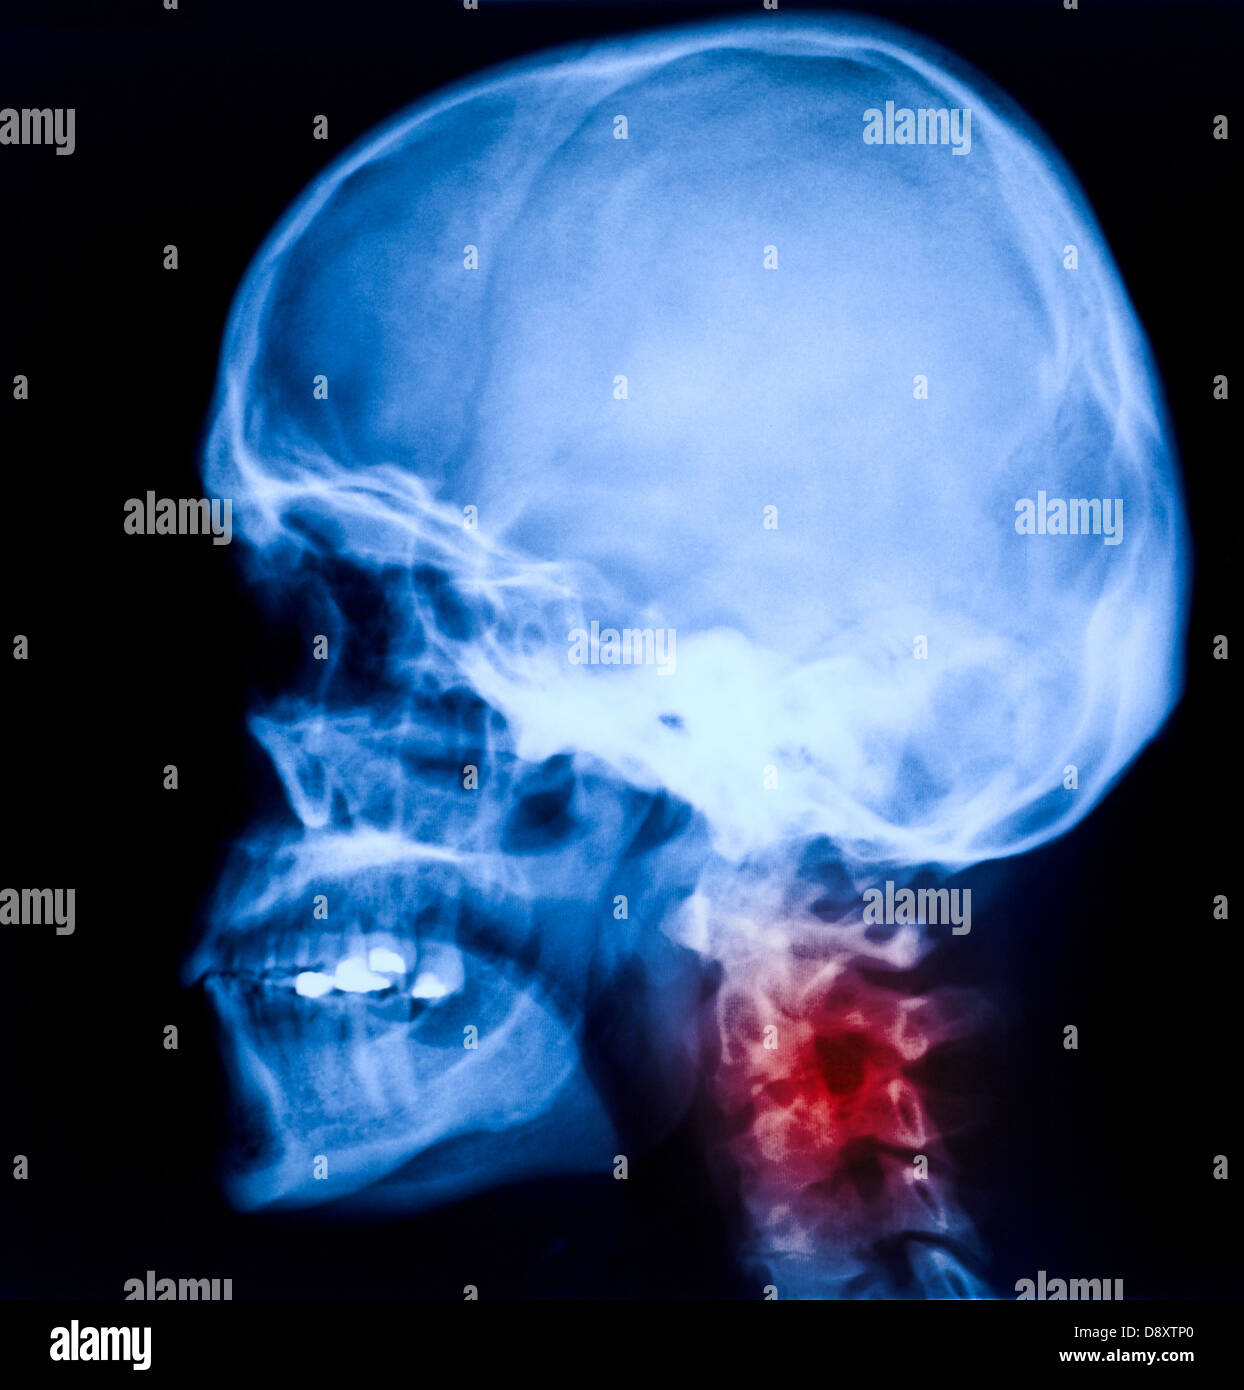

From www.alamy.com

Xray image hires stock photography and images Alamy Potpourri Xray I am very happy with the comments and feedback i have been getting on this 'kind' of videos so i will. Although radiological facilities are easily accessible in high‐income. Chest radiographs (x‐rays) are one of the commonly used strategies. Here is another edition of my radiologic potpourri. Potpourri is frequently used as an air freshener, and many commercially available containers. Potpourri Xray.